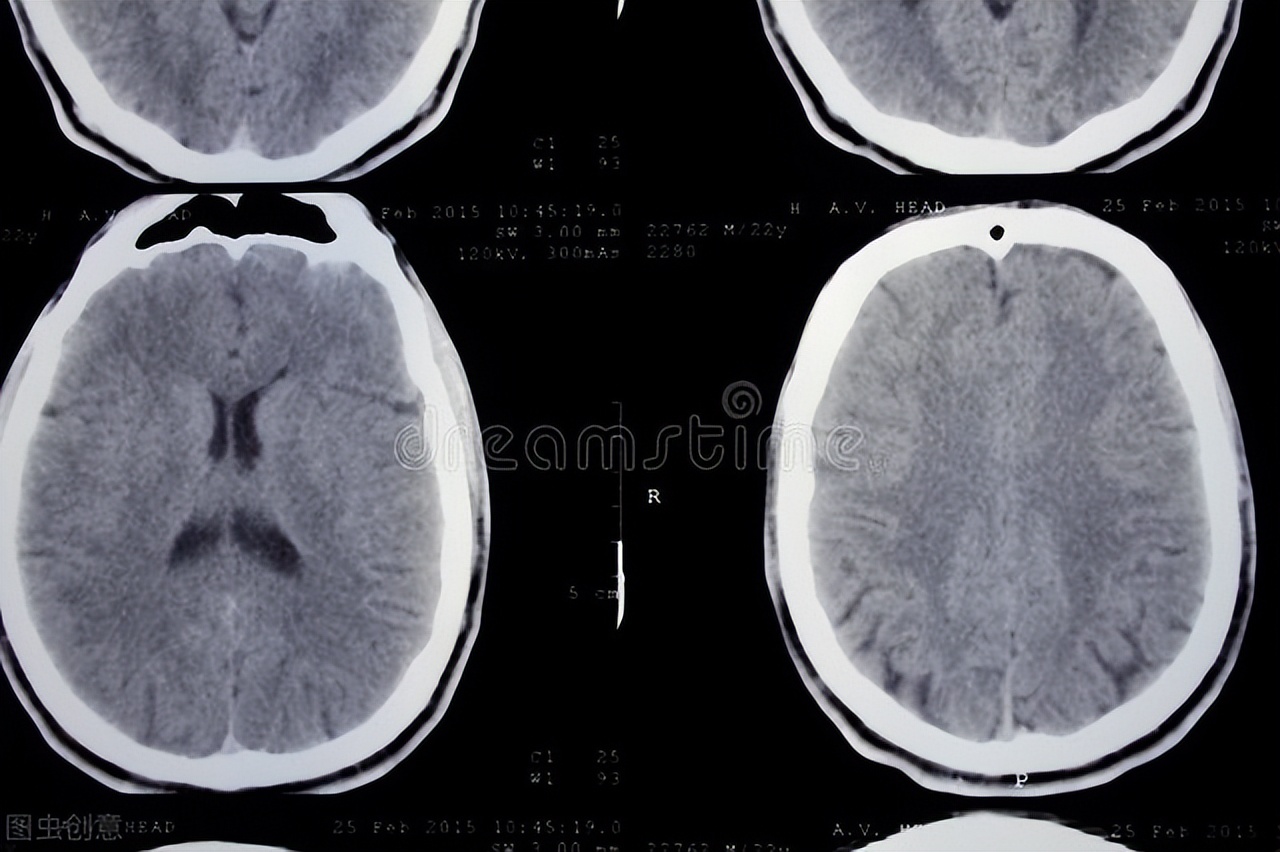

医生丝毫不敢放松,急查头颅CT。

结果一切正常。

头颅CT